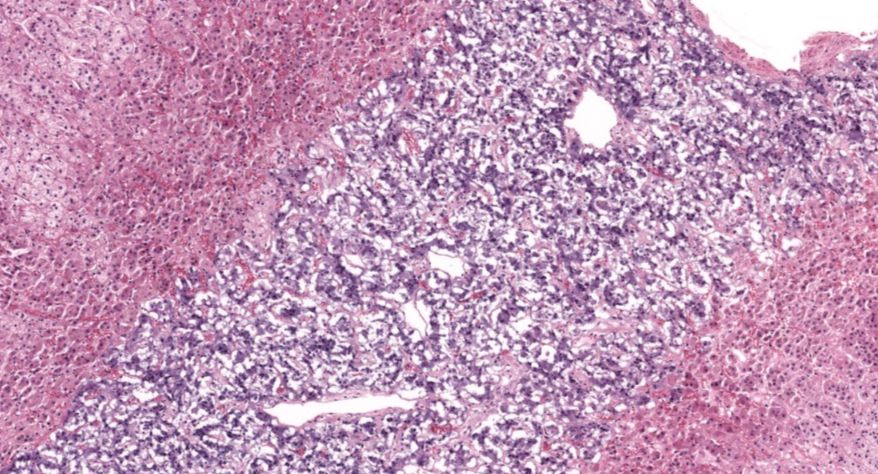

弥漫性非毒性甲状腺肿:甲状腺滤泡明显扩张,内含大量胶质,滤泡上皮细胞受压呈扁平状。部分上皮增生,可见小滤泡和小假乳头形成。

1.全景图

![]()

2.纤维组织包膜

3.滤泡上皮增生

4.滤泡扩张